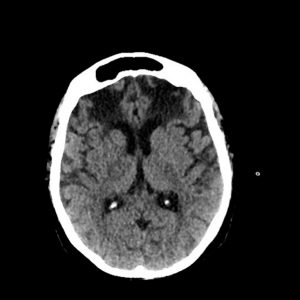

Atrophie cérébrale bi-frontale inhabituelle, à quoi peut-elle être due ?

Cas clinique : Mme B., âgée de 74 ans, est hospitalisée en unité de médecine aiguë gériatrique pour sepsis sévère sur pneumonie à Streptococcus pneumoniae. Cette patiente a des antécédents…